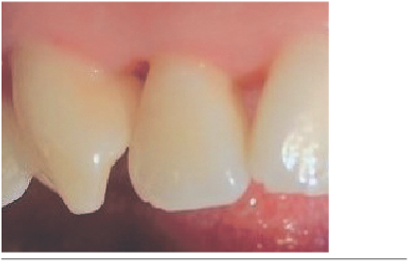

Paciente sexo femenino de 23 años de edad, sin antecedentes mórbidos relevantes y tratada periodontalmente. Presenta defectos de triángulo negro en papilas gingivales del sector anterior del maxilar superior (Figuras 1 y 2).

Las papilas fueron clasificadas según la clasificación de Norland y Tarnow1, dando los siguientes resultados. La papila entre los dientes 1.3 - 1.2 clase III, papila entre 1.2 - 1.1 clase II (Figura 1), papila entre 1.1 - 2.1 clase I, papila entre 2.1 - 2.2 clase I (Figura 2) y papila entre 2.2 - 2.3 clase II.